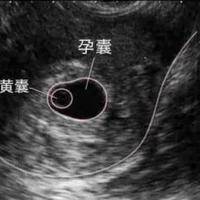

胎心监护是用来查看胎儿在宫内发育状况的手段,能够及时了解胎儿宫内有无缺氧等情况,胎心监护在孕期不可能每次都能过关,很多女性在孕晚期大多都会认为医院的胎心监护是一个坑,主要原因如下,大家可以做个参考。

胎心监护其实是非常重要的一项检测,它可以及时发现胎儿窘迫,以便采取相应措施,降低孕妇和胎儿的风险,大家在做胎心监护的时候尽量去医院进行,这样才能准确掌握胎儿监护指征,从而降低不必要的干预,有任何不适都要及时寻求专业医生帮助。